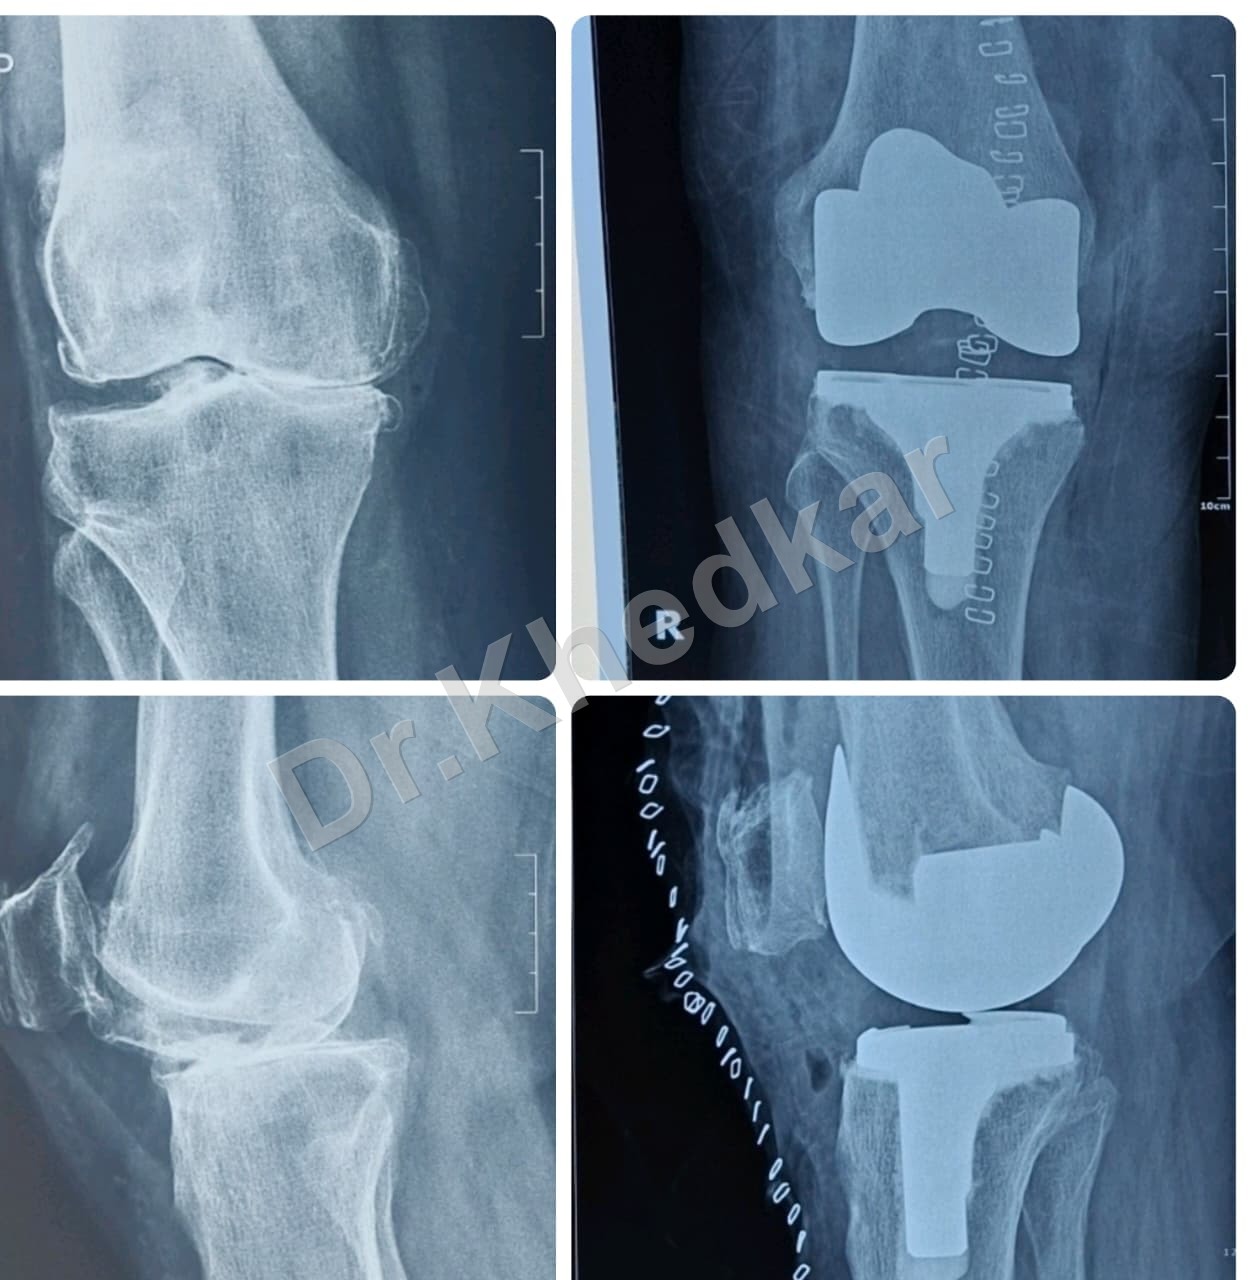

Total Knee Replacement (TKR)

TKR patient care preview

TKR Procedure Thumbnail